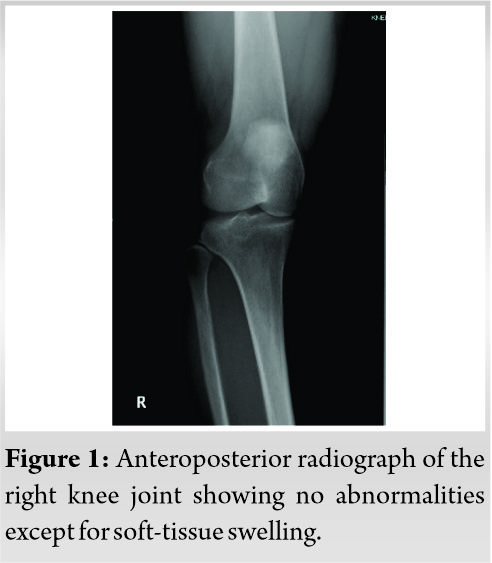

The results of blood tests were essentially normal. X-ray findings of the right knee joint showed no abnormalities. No osteoarthritic change or bone erosion was present. A soft-tissue shadow was not seen (Fig. 1).